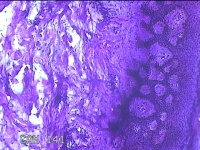

性别

男

年龄

50岁

临床诊断

皮脂腺囊肿

一般病史

发现左侧膝部包块8年余,无明显疼痛及不适。

标本名称

左侧膝部包块

大体所见

灰白暗红色组织3.3x2.3x0.8cm一块,表面带梭形皮肤3.5x1.5cm,皮下见包块3.3x1.5x0.8cm一个,切开包块呈实性,切面灰白粉红色,质软。

图2